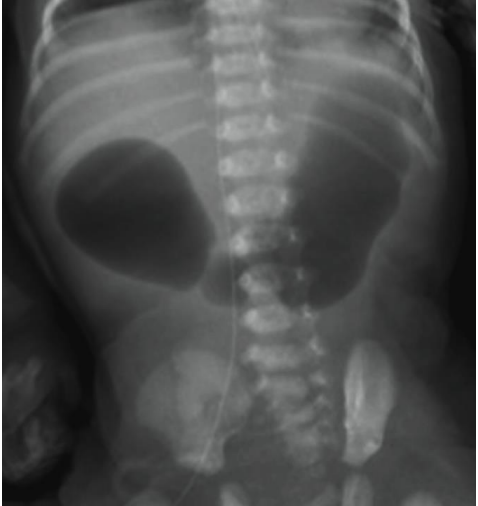

Assinale a alternativa que apresenta qual o sinal representado no estudo de radiografia simples do abdome abaixo.

Provas